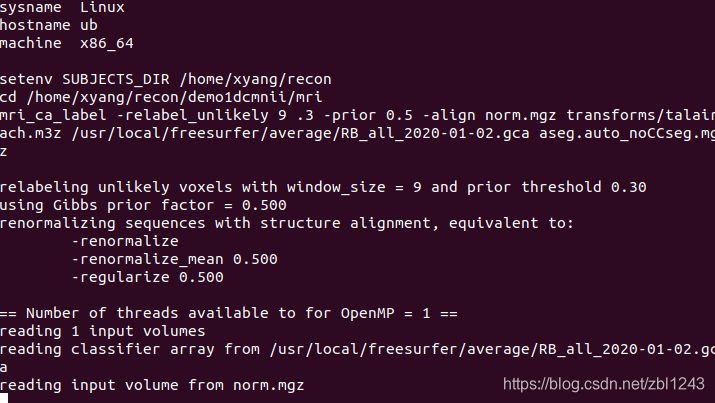

#!/usr/bin/env bash

export SUBJECTS_DIR=/home/recon

for subj in `ls /home/recon/test`

do

recon-all -s $subj -i /home/recon/test/$subj/*.nii -all -qcache

done这个批处理可以操作多个sub用户的nii,比如demo4dcmnii、demo5dcmnii……。注意上面的 ` 符号是反引号,不是单引号。

然后打开命令行,运行sh文件:

:~/recon$ sh recon_all.sh执行会非常非常久

有以下处理过程: